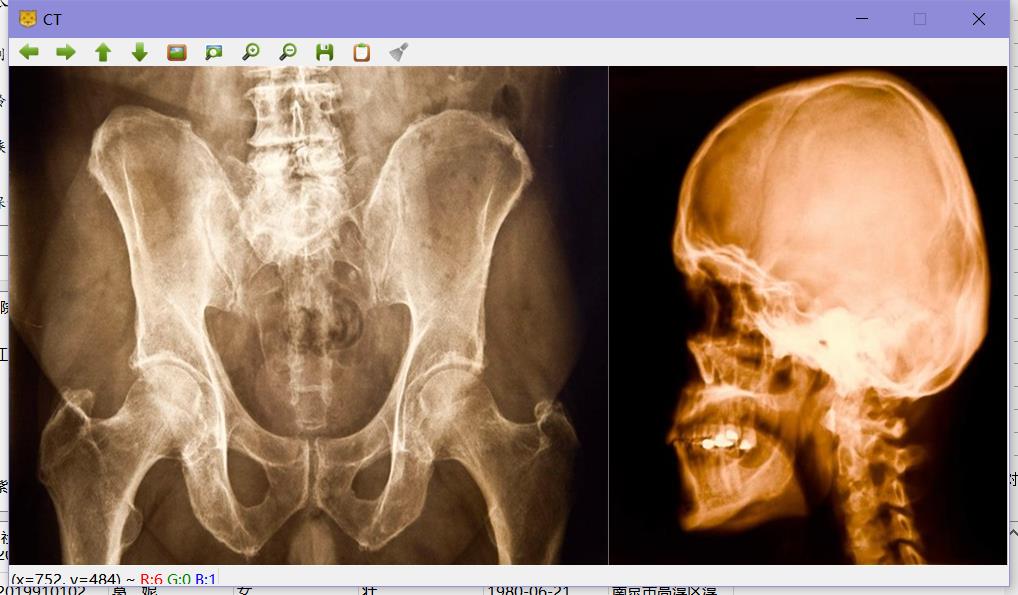

医生可使用该软件查看患者的电子档案,通过查看CT相片和化验单等数据,为患者写诊断结果, 同时CT相片经过特定的图像处理算法处理后可以更加凸显病灶,提高医生的诊断效率。

- 使用OpenCV 的图像处理算法完成病灶检测和细胞计数等功能,对CT照片有很好的处理效果。

检测CT相片中的异物,比如肿瘤,将圈出标记。

使用到的技术:opencv中的霍夫圆检测算法

CT相片处理